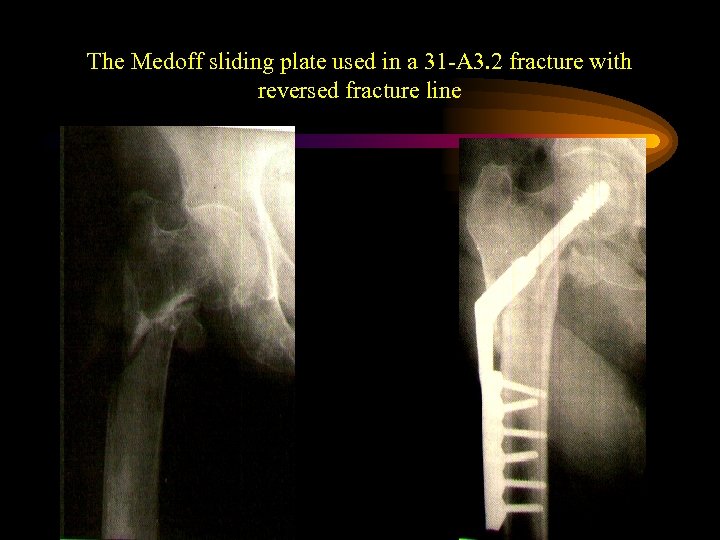

The Medoff sliding plate • A sliding screw plate system allowing sintering along the neck axis as well as along the femoral axis

The Medoff sliding plate • A sliding screw plate system allowing sintering along the neck axis as well as along the femoral axis

The Medoff sliding plate used in a 31 -A 3. 2 fracture with reversed fracture line

The Medoff sliding plate used in a 31 -A 3. 2 fracture with reversed fracture line